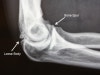

X-ray : 팔꿈치 퇴행성 관절염(Elbow degenerative arthritis)

주관절의 AP, lateral view만으로 충분히 진단이 이루어집니다.

골극, 관절간격 좁아짐이 나타납니다.

주관절의 앞쪽 및 뒤쪽에 다발성 유리체가 보일 수 있습니다.